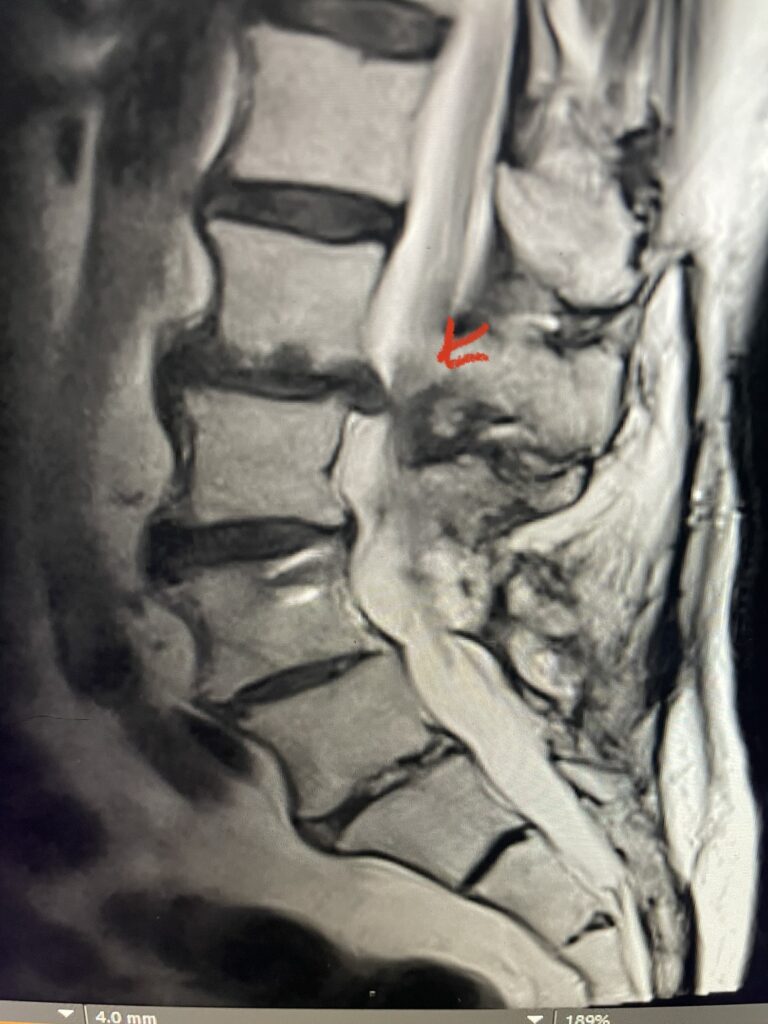

The patient had failed all means of conservative management including Physical Therapy and epidurals. He had an extensive medical history including stroke, cardiac stents, diabetes on insulin, hypertension, hypercholesterolemia, and kidney disease. Since he had a prior fusion with instrumentation for L4-S1, it was interesting that the patient had not developed significant next segment stenosis at L3-4. However, CT analysis (Fig. 2) demonstrated a partial fusion that extended from L3 to L4 which prevented abnormal motion.

Fig 2: Coronal lumbar CT demonstrating L4-S1 fusion with instrumentation with some incomplete bony fusion to the L3-4 segment (red arrow)